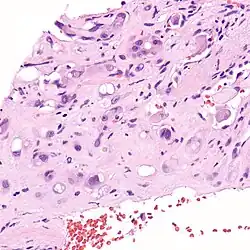

Micrograph of an epithelioid hemangioendothelioma of the liver.

Epithelioid hemangioendothelioma (EHE) is a rare tumor, first characterized by Sharon Weiss and Franz Enzinger in 1982[1] that both clinically and histologically is intermediate between angiosarcoma and hemangioma. However, a distinct, disease-defining genetic alteration recently described for EHE indicates that it is an entirely separate entity from both angiosarcoma and hemangioma.

EHE is a soft tissue sarcoma and is generally considered a vascular cancer insofar as the ‘lesional’ cells have surface markers typical of endothelial cells (cells lining the interior of blood vessels). EHE was originally described as occurring most commonly in the veins of the extremities (arms and legs) and two organs, the liver[2] and lungs. It has since been described in organs throughout the body. In addition to liver and lungs, bones and skin have been the most frequent organs.